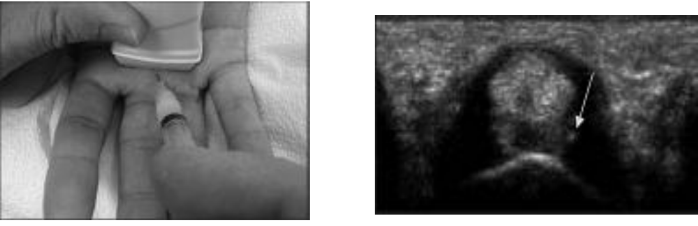

- Siêu âm xác định vị trí cần tiêm: đặt đầu dò ở lát cắt ngang qua khớp bàn ngóntay, vị trí tiêm là đưa kim vào được chính xác vùng tam giác ngay dưới ròng rọc A1. Vùng tam giác này được giới hạn bởi gân gấp chung các ngón, nền xương bàn ngón tay và khoảng cách từ khớp bàn ngón đến ròng rọc.

- Tiến hành chọc kim qua da, hướng kim tạo một góc 30 độ so với mặt phẳng nằm ngang và đồng thời quan sát trên màn hình. Khi kim vào đúng vị trí tam giác ở phía bên trái của trung tâm màn hình thì tiến hành tiêm thuốc.

Hình minh họa: Tiêm gân gấp ngón III dưới hướng dẫn của siêu âm. Nguồn: internet.